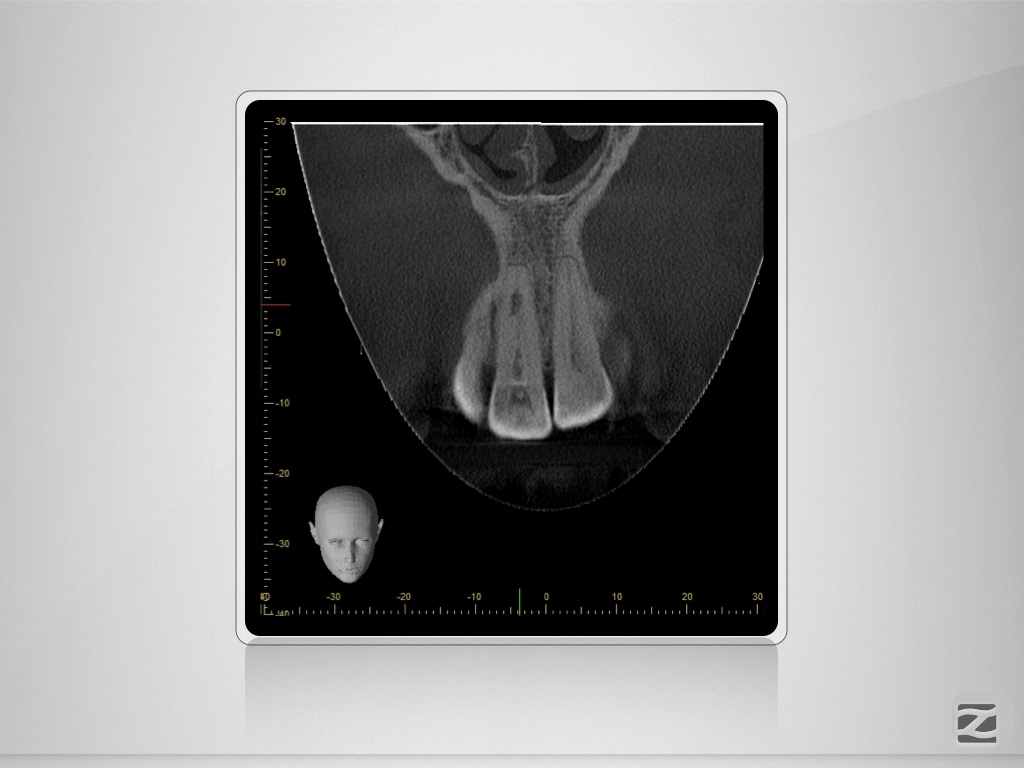

11D.002

1024 × 768

Unverhofft und nicht oft.